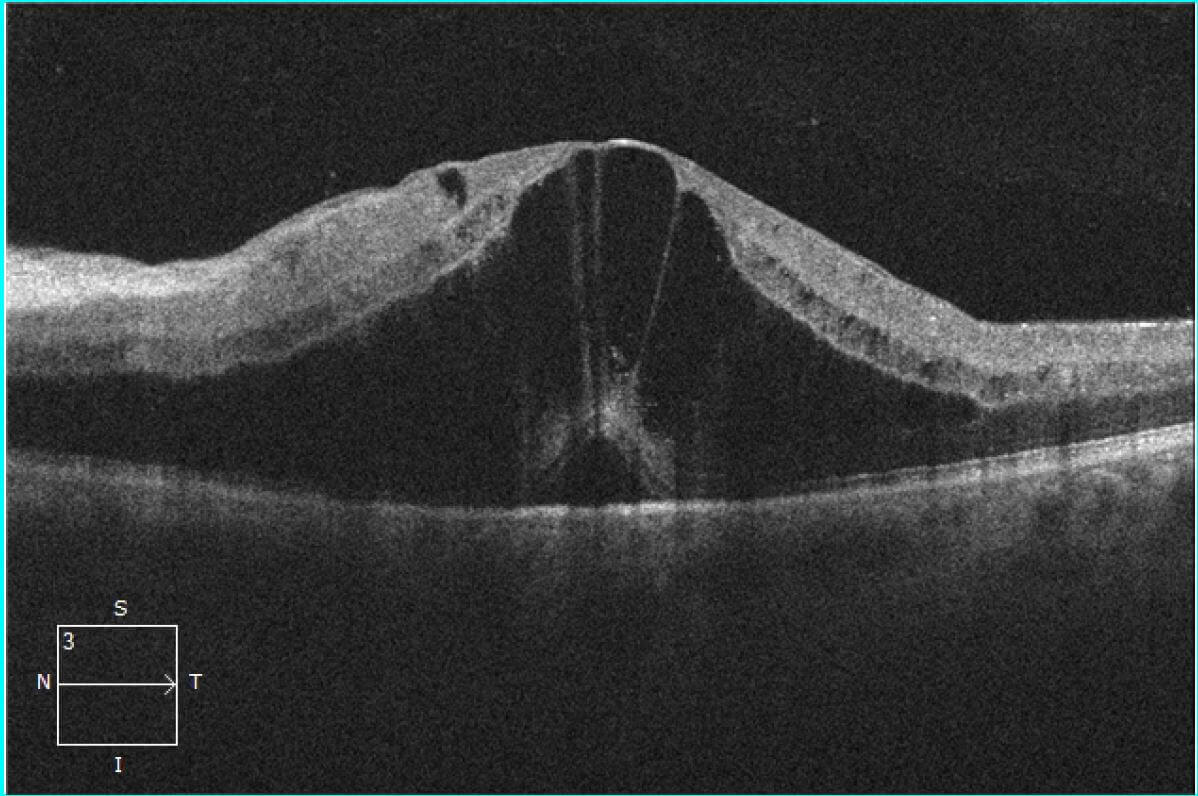

This article describes optical coherence tomography (OCT) findings in patients with central retinal artery occlusion by conducting a retrospective review of two cases. Central retinal artery occlusion shows a distinct pattern on OCT images. In the acute phase, OCT images demonstrate the increased reflectivity and thickness of the inner retina.

Occlusion of the central retinal artery (CRAO) and its branches (BRAO) leads to the formation of acute tissue ischemia, giving a specific OCT picture - pronounced hyperreflectivity, with loss of.

Purpose To study the optical coherence tomography (OCT) changes in eyes with acute central retinal artery occlusion (CRAO) of different severity and at different disease stages. Methods The study included acute CRAO cases of < 7 days duration, imaged on OCT at various time points. Based on the OCT findings at presentation, cases were classified into three severity groups: mild, moderate, and.